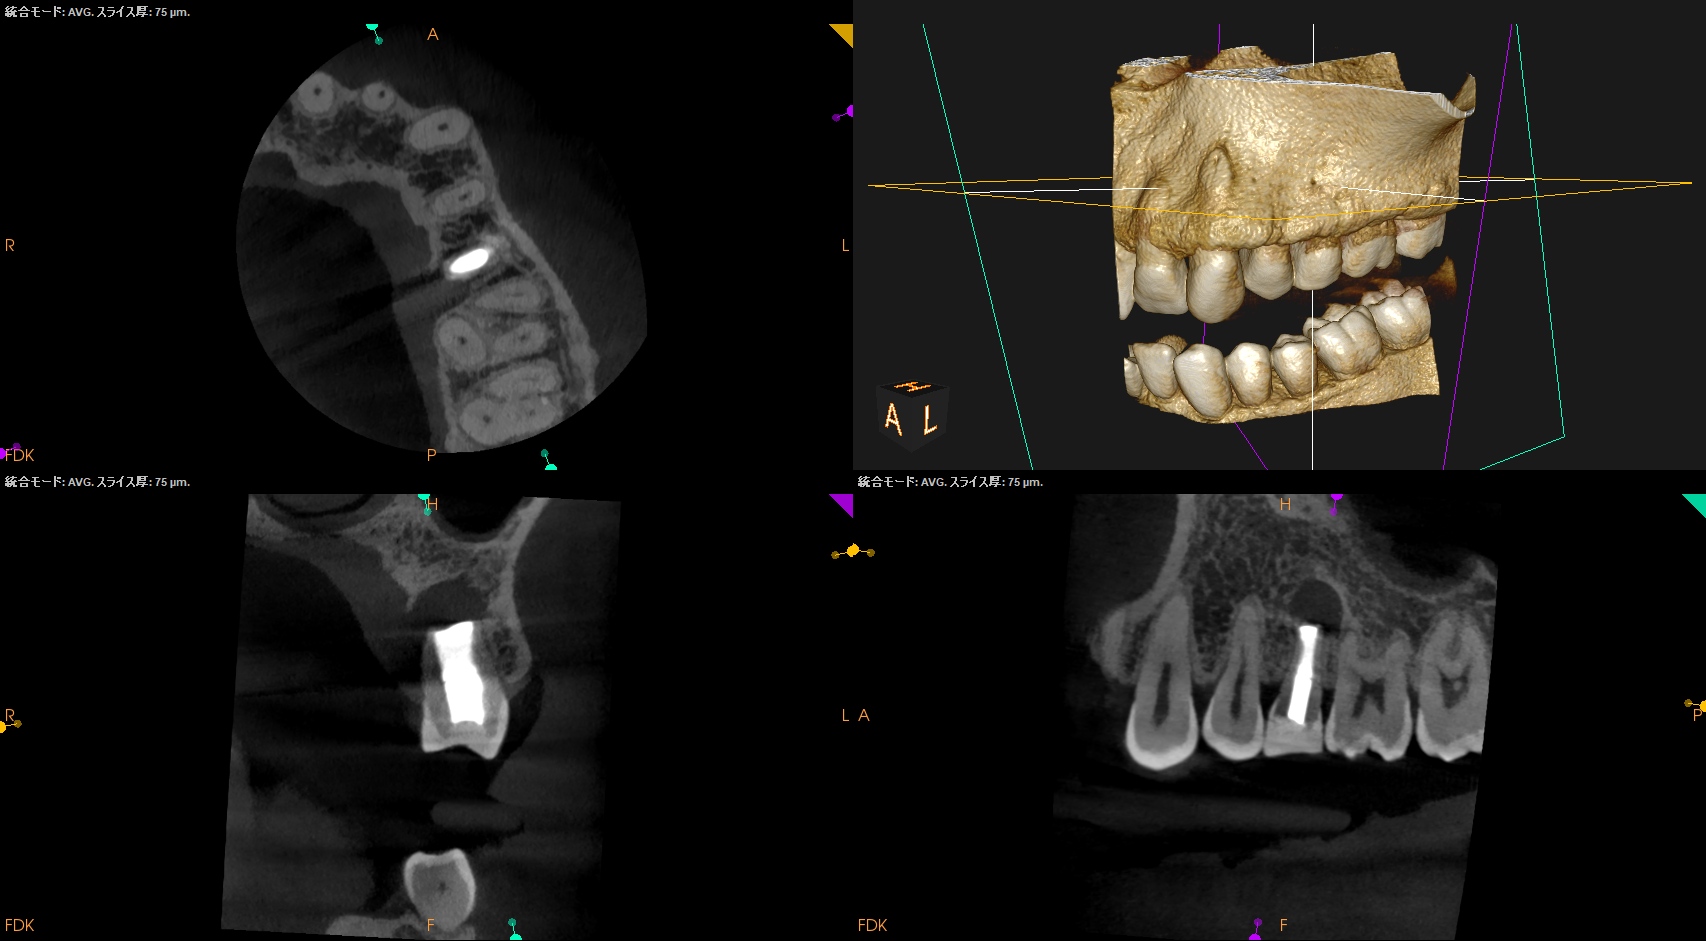

PA,CBCTも撮影した。

折れている!と言われかねない状況である。

が、本当に折れているかどうか?は、抜歯して歯牙を直視しないと分からない。

術前のCBCTからVertical Root Fractureも疑われるので、メチレンブルーで染め出して歯牙を精査した。

術後にPA,CBCTを撮影した。

問題はないだろう。